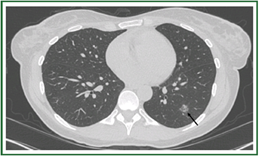

TOP2、肺结节筛查最优的检查方法是什么?

张伟:肺结节筛查常见的方法包括胸部平片和胸部CT(如图)。平片检查由于前后重叠,分辨率低,以至于肺内早期病变无法检出。而CT分辨率高,并且是一种螺旋式的扫描,就像切面包一样,一层一层把肺切开,可以显示非常小,密度非常淡的早期病变。所以, CT检查是肺结节筛查的最优检查方法。